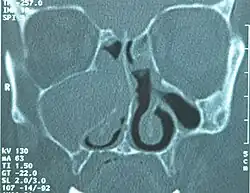

![]() TK śuzowiaka prawej zatoki szczękowej, powodującego wybrzuszenie wyrostka haczykowatego kości sitowej | |

Diagnostyka jedynie radiologiczna. Daje to obraz zakresu ekspansji śluzowiaka, jej położenie, stosunki anatomiczne z innymi strukturami, co jest kluczowe dla zaplanowania leczenia operacyjnego na oddziale otolaryngologicznym. Podstawowym badaniem jest TK zatok przynosowych w kilku projekcjach. Wartość diagnostyczna zwykłego zdjęcia rentgenowskiego zatok przynosowych jest oceniana jako raczej znikoma. Badanie MRI pokazujące bardzo dobrze tkanki miękkie uzupełnia jedynie badanie TK, gdyż nie widać na nim kości, co jest ważne dla określenia np. zniszczenia kości przez śluzowiaka.